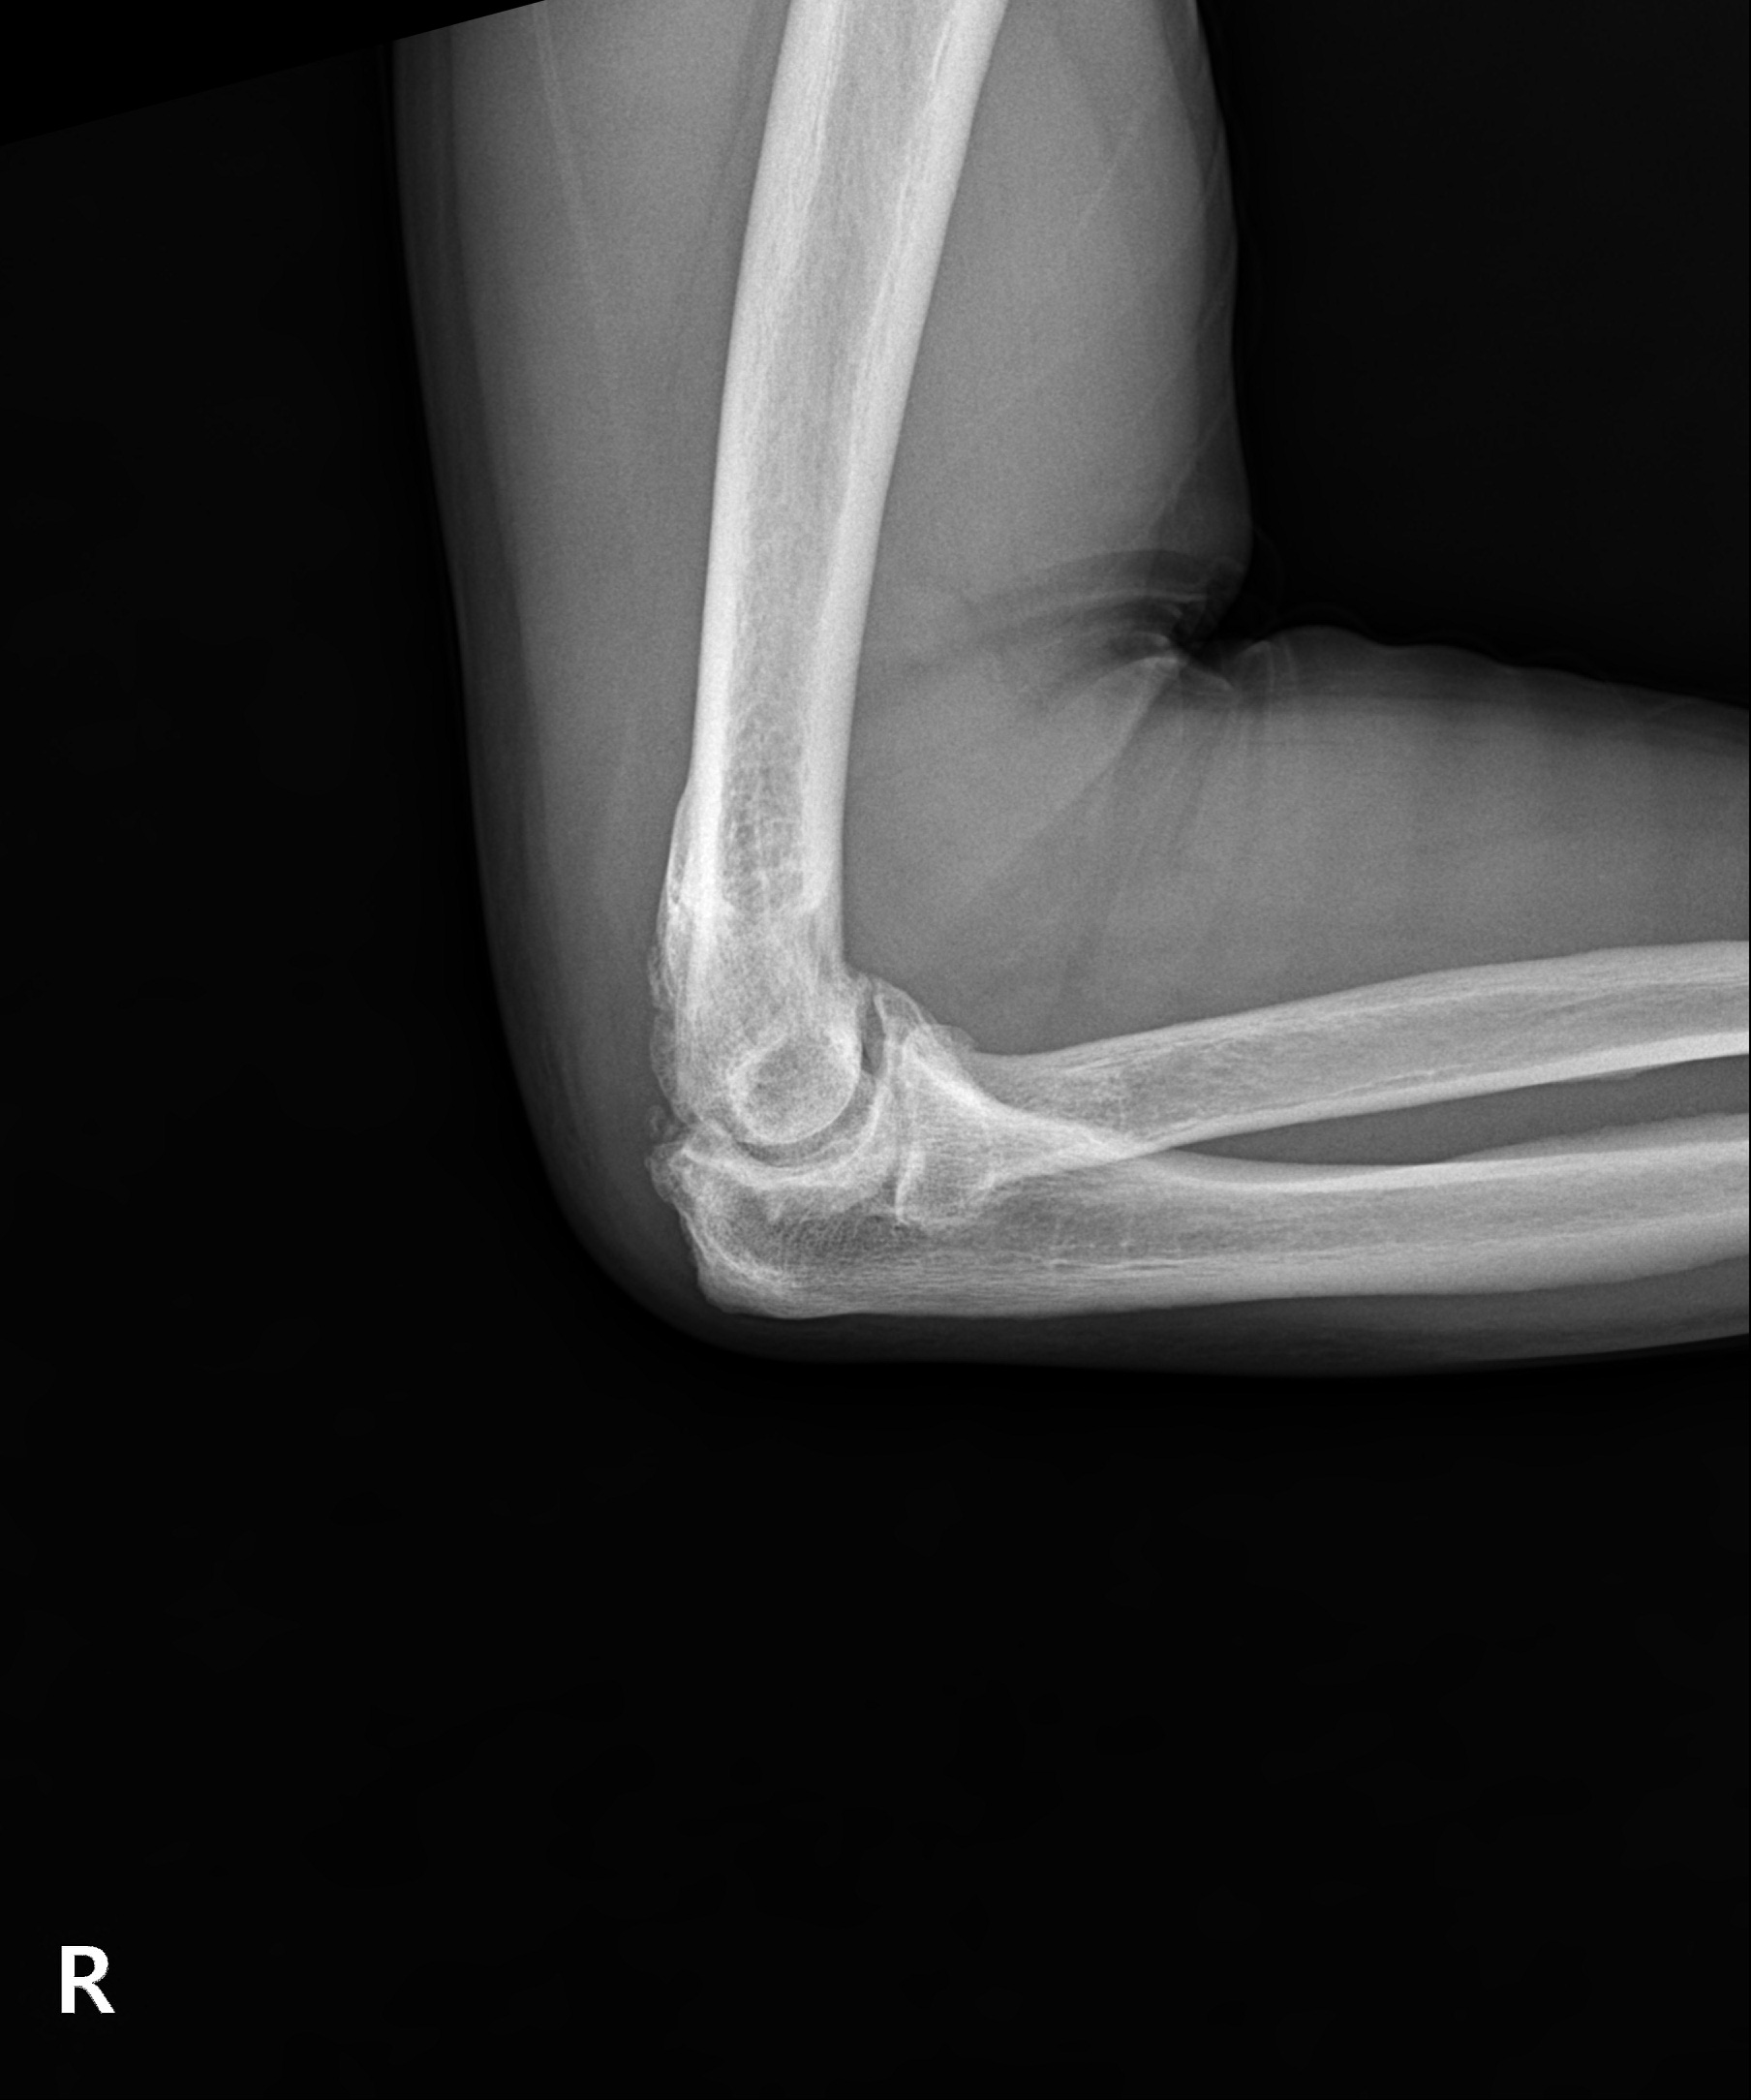

다른 부위 관절염처럼 팔꿈치 관절을 오랜 시간 과사용하여 관절이 손상되고 염증이 발생하는 질환입니다. 팔꿈치관절염은 시간이 지나며 점차 연골이 닳고 뼈가 자라나는 골극이 발생해 관절 가동 범위가 줄어들며 변형과 통증을 악화시킬 수 있습니다.

이미 관절 가동 범위에 제한이 온 팔꿈치 관절염은 뼈가 자라고

유리체 등이 관절면을 덮은 경우가 대부분으로 수술적 치료가 필요

관절내시경을 통해 자라난 뼈 조각과 관절 내 유리체를 제거하며

심한 경우 절개 수술이 함께 필요할 수 있습니다.